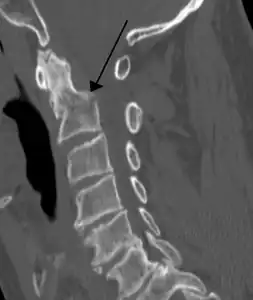

![]() | |

| A fracture of the base of the dens (a part of C2) as seen on CT. | |